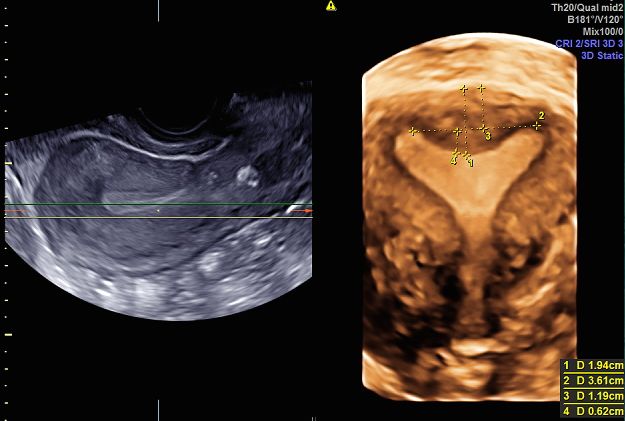

Sono esperta in ecografia 3D (tridimensionale) di cui sono stata docente a livello nazionale ed internazionale per oltre 20 aa, rivestendo incarichi nazionali nell'ambito della Società di Ecografia in Ostetricia e Ginecologia (SIEOG).

• malformazioni uterine

• setto uterino

• utero bicorne

ecografia 3D Da 260 €